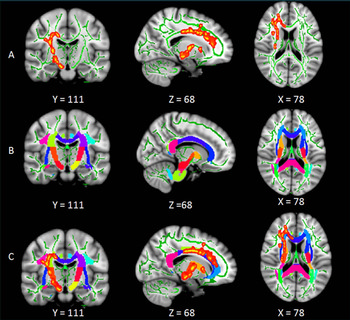

White matter (WM) tracts related to regulation of sleep and wakefulness, and limbic cognitive and sensorimotor regions, are disrupted in the right brain in patients with primary insomnia. The reduced integrity of these WM tracts may be because of loss of myelination, according to new research published in the journal, Radiology.

Primary insomnia patients had lower fractional anisotropy (FA) values mainly in the right anterior limb of the internal capsule, right posterior limb of the internal capsule, right anterior corona radiata, right superior corona radiata, right superior longitudinal fasciculus, body of the corpus callosum, and right thalamus.